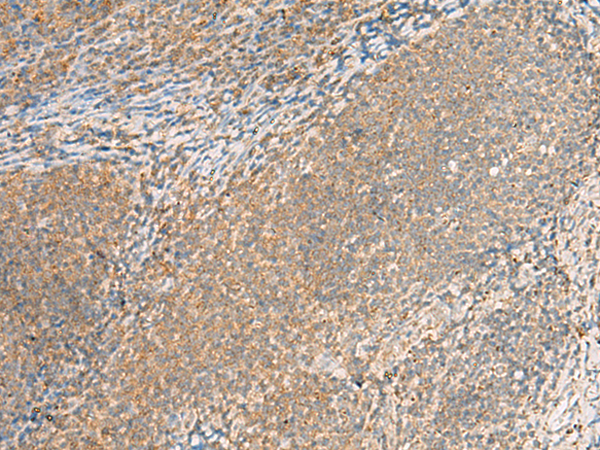

分类: 科研抗体货号: P09903别名: CTLH; GID2; RMD5; GID2A; p44CTLH应用: IHC反应种属: Human, Mouse